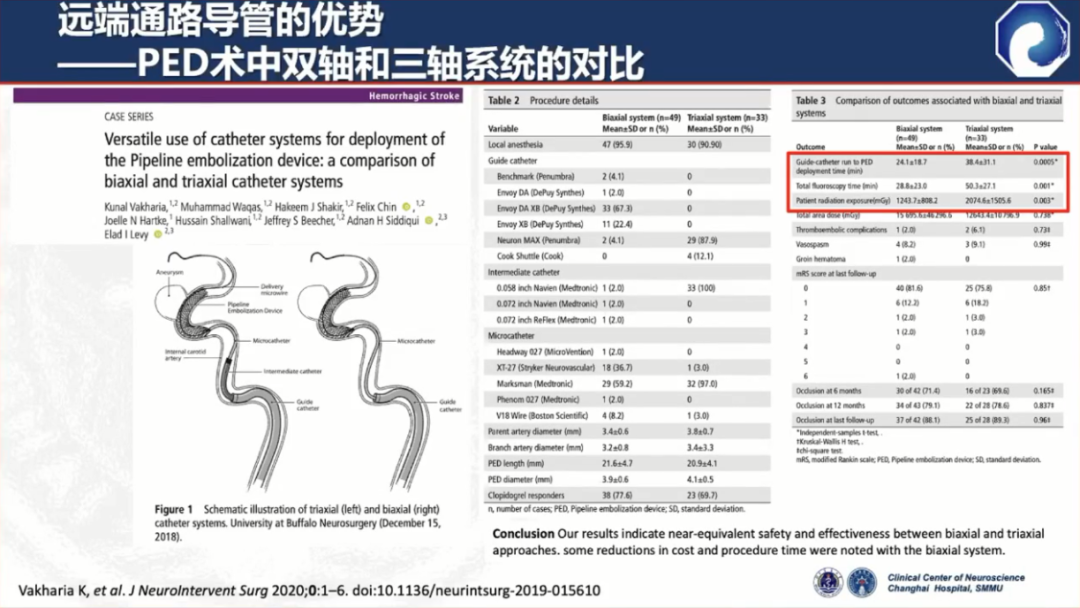

此外,中间导管的支撑力比较差,近端需加长鞘或8F Guiding做支撑,需三轴系统

三轴系统的缺点:

与三轴系统相比,双轴系统显著缩短了手术时间,降低潜在并发症发生率